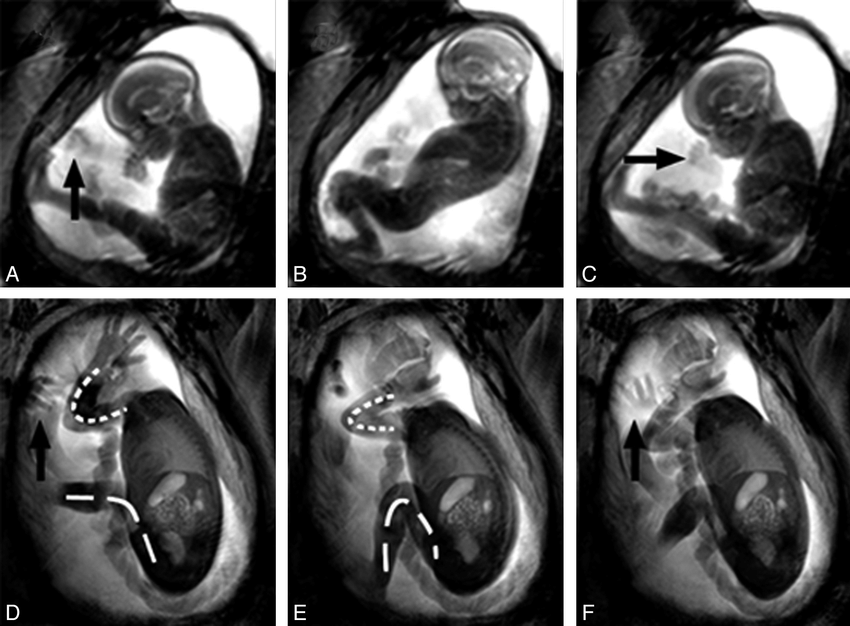

15. Paru-paru

Sudah mendekati akhir dari tahap pertumbuhan. Paru-paru adalah organ terakhir yang berkembang dengan sempurna. Alasannya, organ tersebut sebenarnya tidak terlalu penting untuk fetus yang bernapas dalam cairan ketuban.

Sel pembentuk paru-paru mulai memproduksi zat surfactant yang mampu memperbesar diri di minggu ke-23. Ini akan mempersiapkan fetus untuk menghadapi dunia luar.